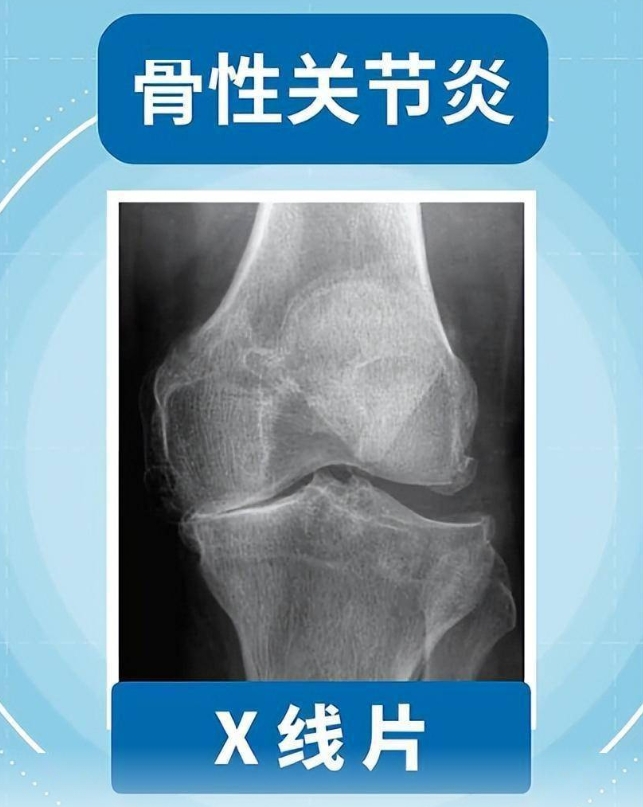

网易新闻网页版:且行且珍“膝”!膝盖脆弱的你,请收好这份护“膝”秘籍